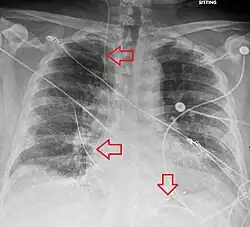

Uma radiografia após o procedimento é obtida para confirmar a colocação do eletrodo de estimulação e descartar complicações como pneumotórax [2][3]. A desfibrilação e a cardioversão ainda podem ser realizadas em alguém com marcapasso temporário[2].